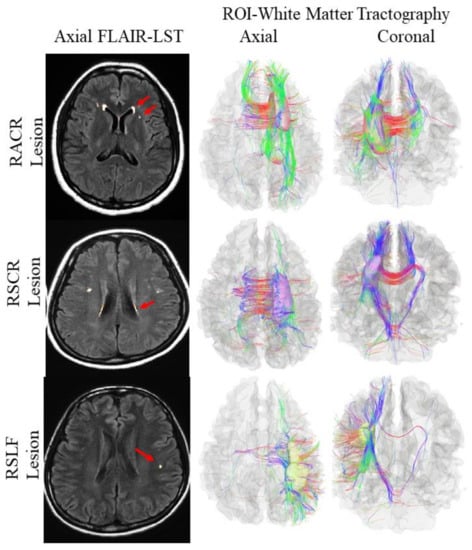

Three bilateral white matter tracts (bilateral anterior corona radiata, ACR; superior corona radiata, SCR; and superior longitudinal fasciculus, SLF) were chosen based on the prevalence of WMHs (location-wise), as seen in the MRI brain images of the study subjects. Therefore, six ROIs were selected, regarding the presence of WMHs in specific tracts: right ACR (RACR) (n = 7), left ACR (LACR) (n = 7), right SCR (RSCR) (n = 4), left SCR (LSCR) (n = 4), right SLF (RSLF) (n = 5), and left SLF (LSLF) (n = 3) (see Figure 1). White matter integrity was defined by the value of diffusion parameters of certain white matter tracts, such as (1) fractional anisotropy (FA), where lower FA signifies reduced white matter integrity due to reduced restriction in molecular motion following disruption in axonal cell membranes and myelin sheathes [36,37]; (2) mean diffusivity (MD), where increased MD also signifies reduced white matter integrity following an increase in mean molecular motion concerning disruption in cellular properties (i.e., integrity and size) [37,38]; and (3) radial diffusivity (RD) and axial diffusivity (AD), defined by the rate of diffusion along cellular axes [39], where RD/AD varies across brain regions [40].

Figure 1. From left: the first row shows fluid attenuated inversion recovery (FLAIR) images with white matter hyperintensities (WMHs) voxel outputs from the lesion segmentation tool (LST) showing right anterior corona radiata (RACR) lesion (red arrow) and RACR tractography (axial and coronal view). The second row shows FLAIR images with WMHs voxel outputs from the LST showing right superior corona radiata (RSCR) lesion (red arrow) and RSCR tractography (axial and coronal view). The third row shows FLAIR images with WMHs voxel outputs from the LST showing right superior longitudinal fasciculus (RSLF) lesion (red arrow) and RSLF tractography (axial and coronal view). The blue, red, and green colors on the right figures represent white matter fibers running along the inferior–superior, right–left, and anterior–posterior orientations, respectively. Notes: LST followed the native Statistical Parametric Mapping (SPM) and Matrix Laboratory (MATLAB) orientations for producing JPEG images; hence, the original radiological view (left on right) obtained from the magnetic resonance imaging (MRI) scanner was shifted to neurological view (right on right) as a reminder of viewing interpretation. FLAIR, fluid-attenuated inverse recovery; RACR, right anterior corona radiata; RSLF, right superior longitudinal fasciculus; RSCR, right superior corona radiata; ROI, region of interest.